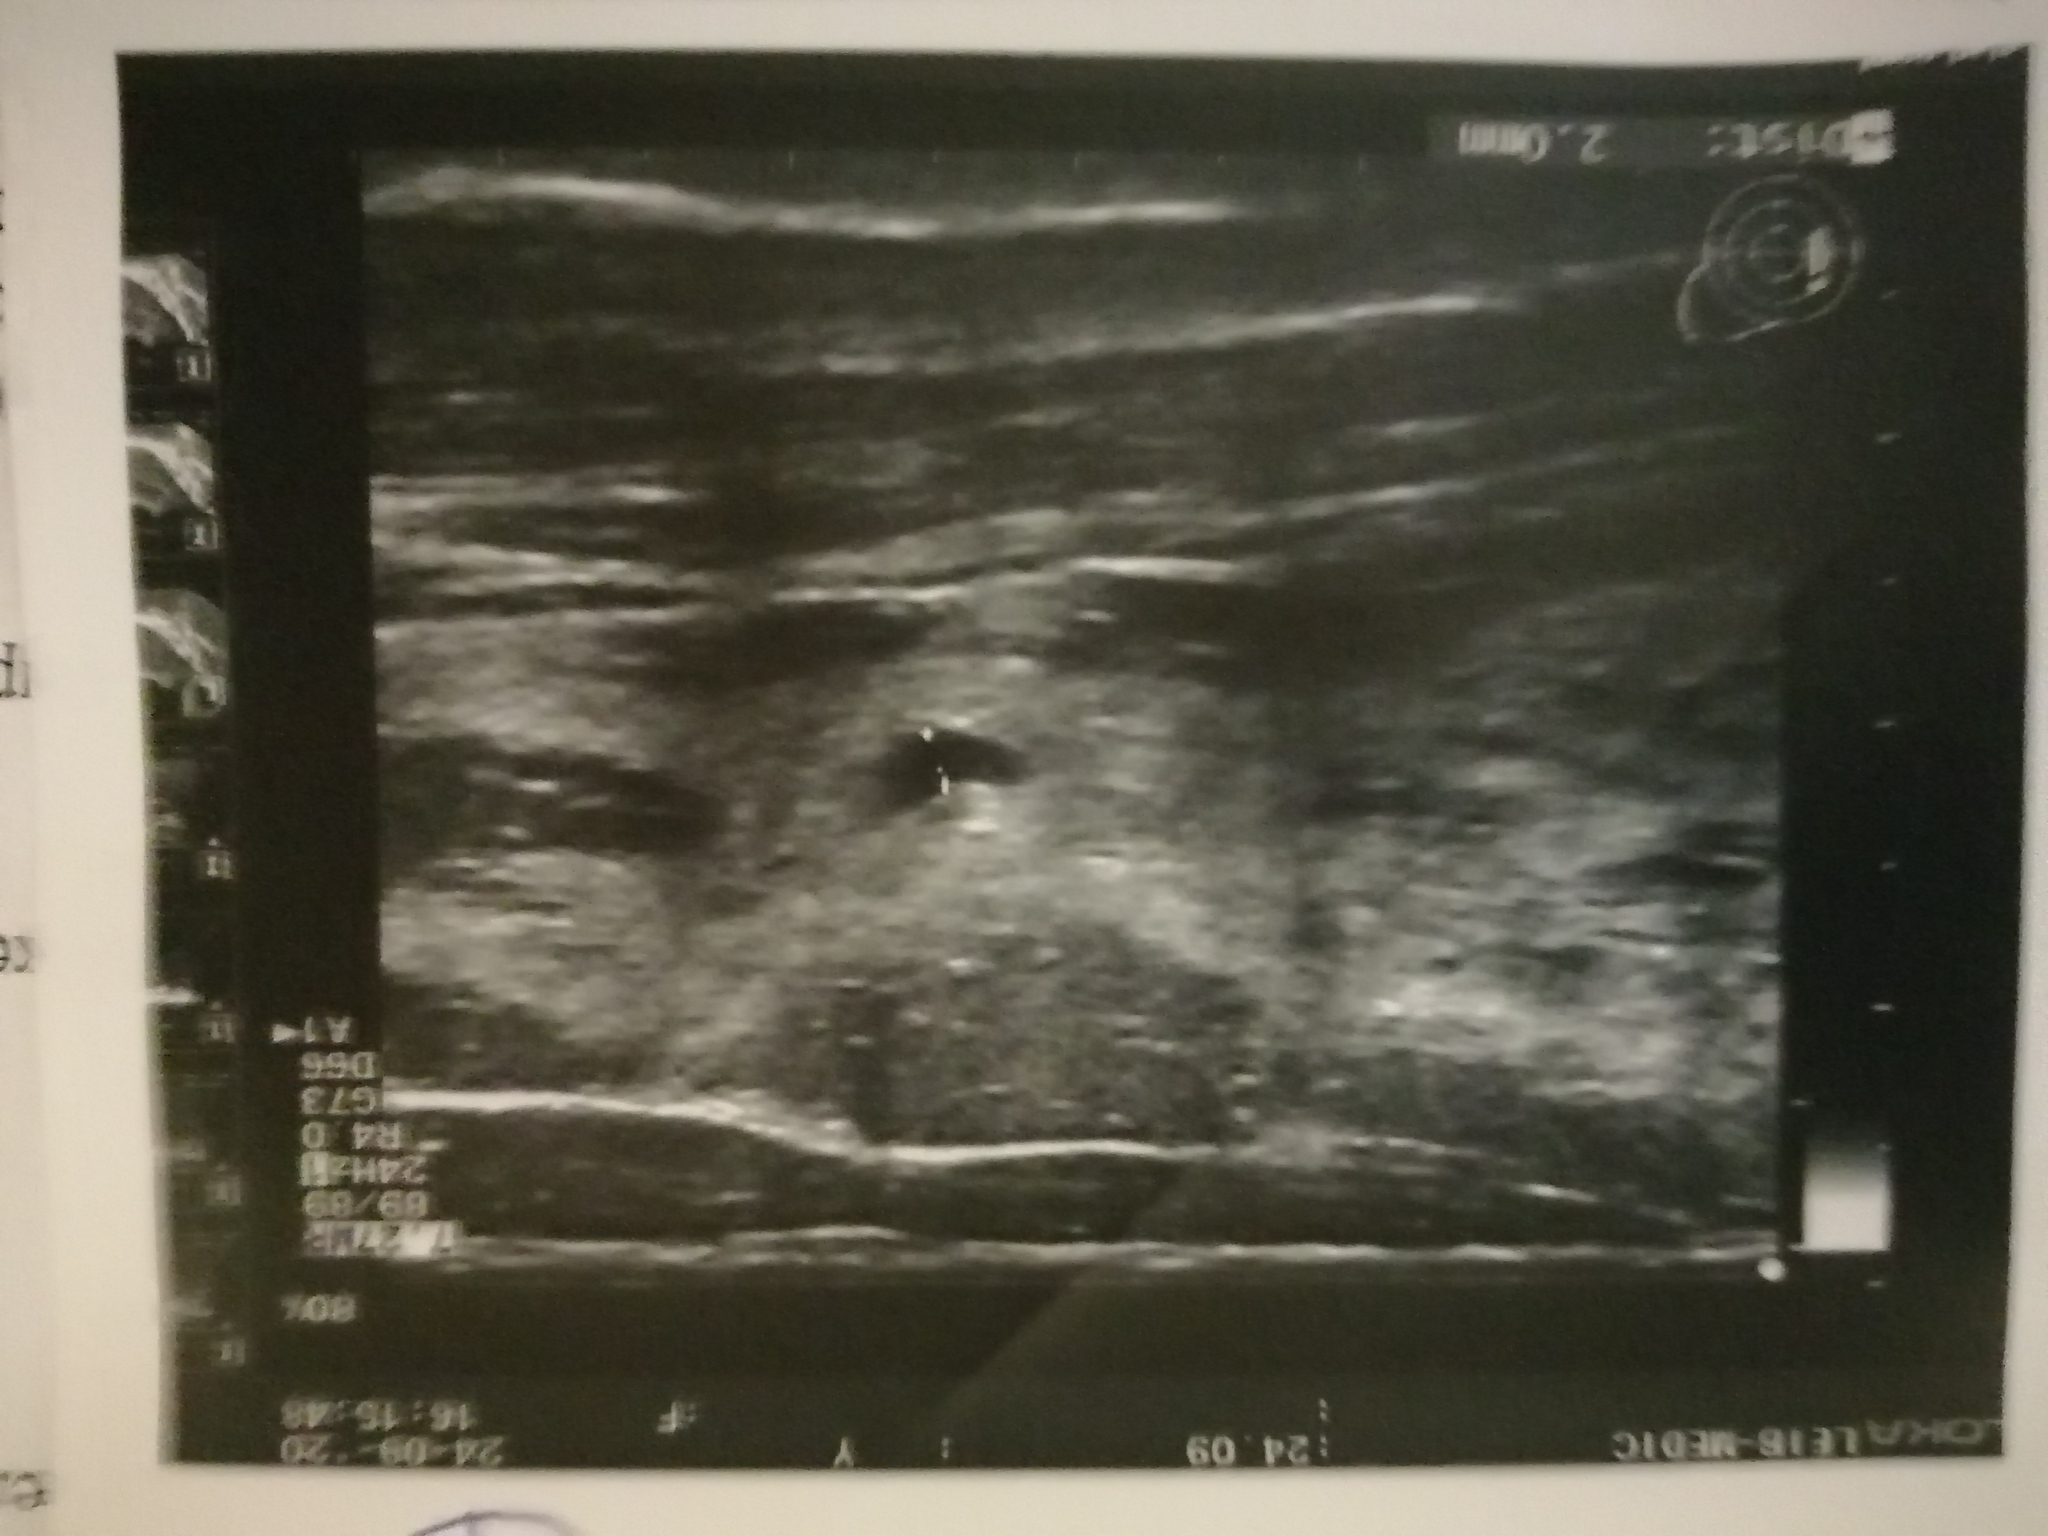

Пол года назад умерла тёща от рака молочной железы. Недавно с супругой ездили на дальняк (1000 км туда-обратно), она была за рулем. После долгой дороги у неё заболела подмышка. Прошло 3 месяца после этой поездки, боль не прошла. Сходила на УЗИ, нашли вроде как уплотнение в груди. Сказали ехать к мамологу. Супруга после этого УЗИ ходит сама не своя и плачет постоянно. Ничего не говорит. Я конечно грешу на то, что после смерти её мамы она в стрессе и все такое. Пока она в душ ходила, сфоткал документы из больницы. Будут во вложении. Подскажите пожалуйста, что это такое и чего ждать и на что это похоже, потому, что она молчит и на мои вопросы не отвечает. Заранее всем спасибо!